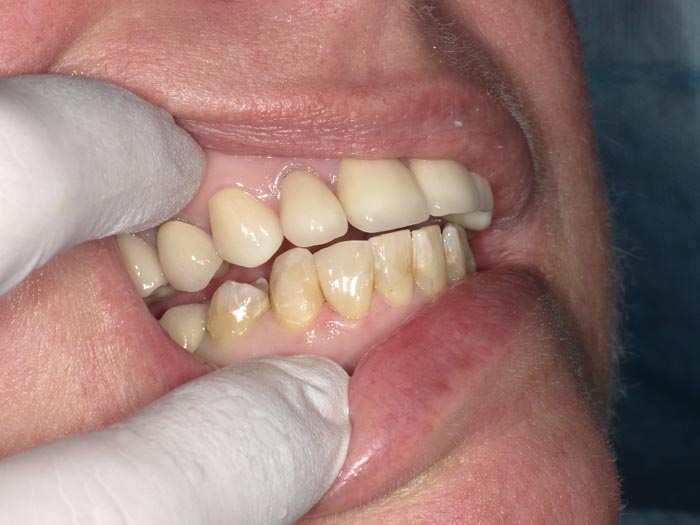

Case 2

A 52-year-old patient presented with failing composite on #26. We see this often; it indicates microleakage at the material/tooth interface because of degradation of the bonding agent.

• Figure 7

• Figure 8

• Figure 9

• Figure 10